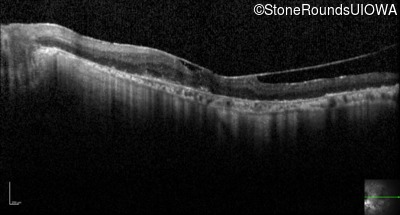

Optical Coherence Tomography - Right - 3/120

Exemplar / OCT Stack